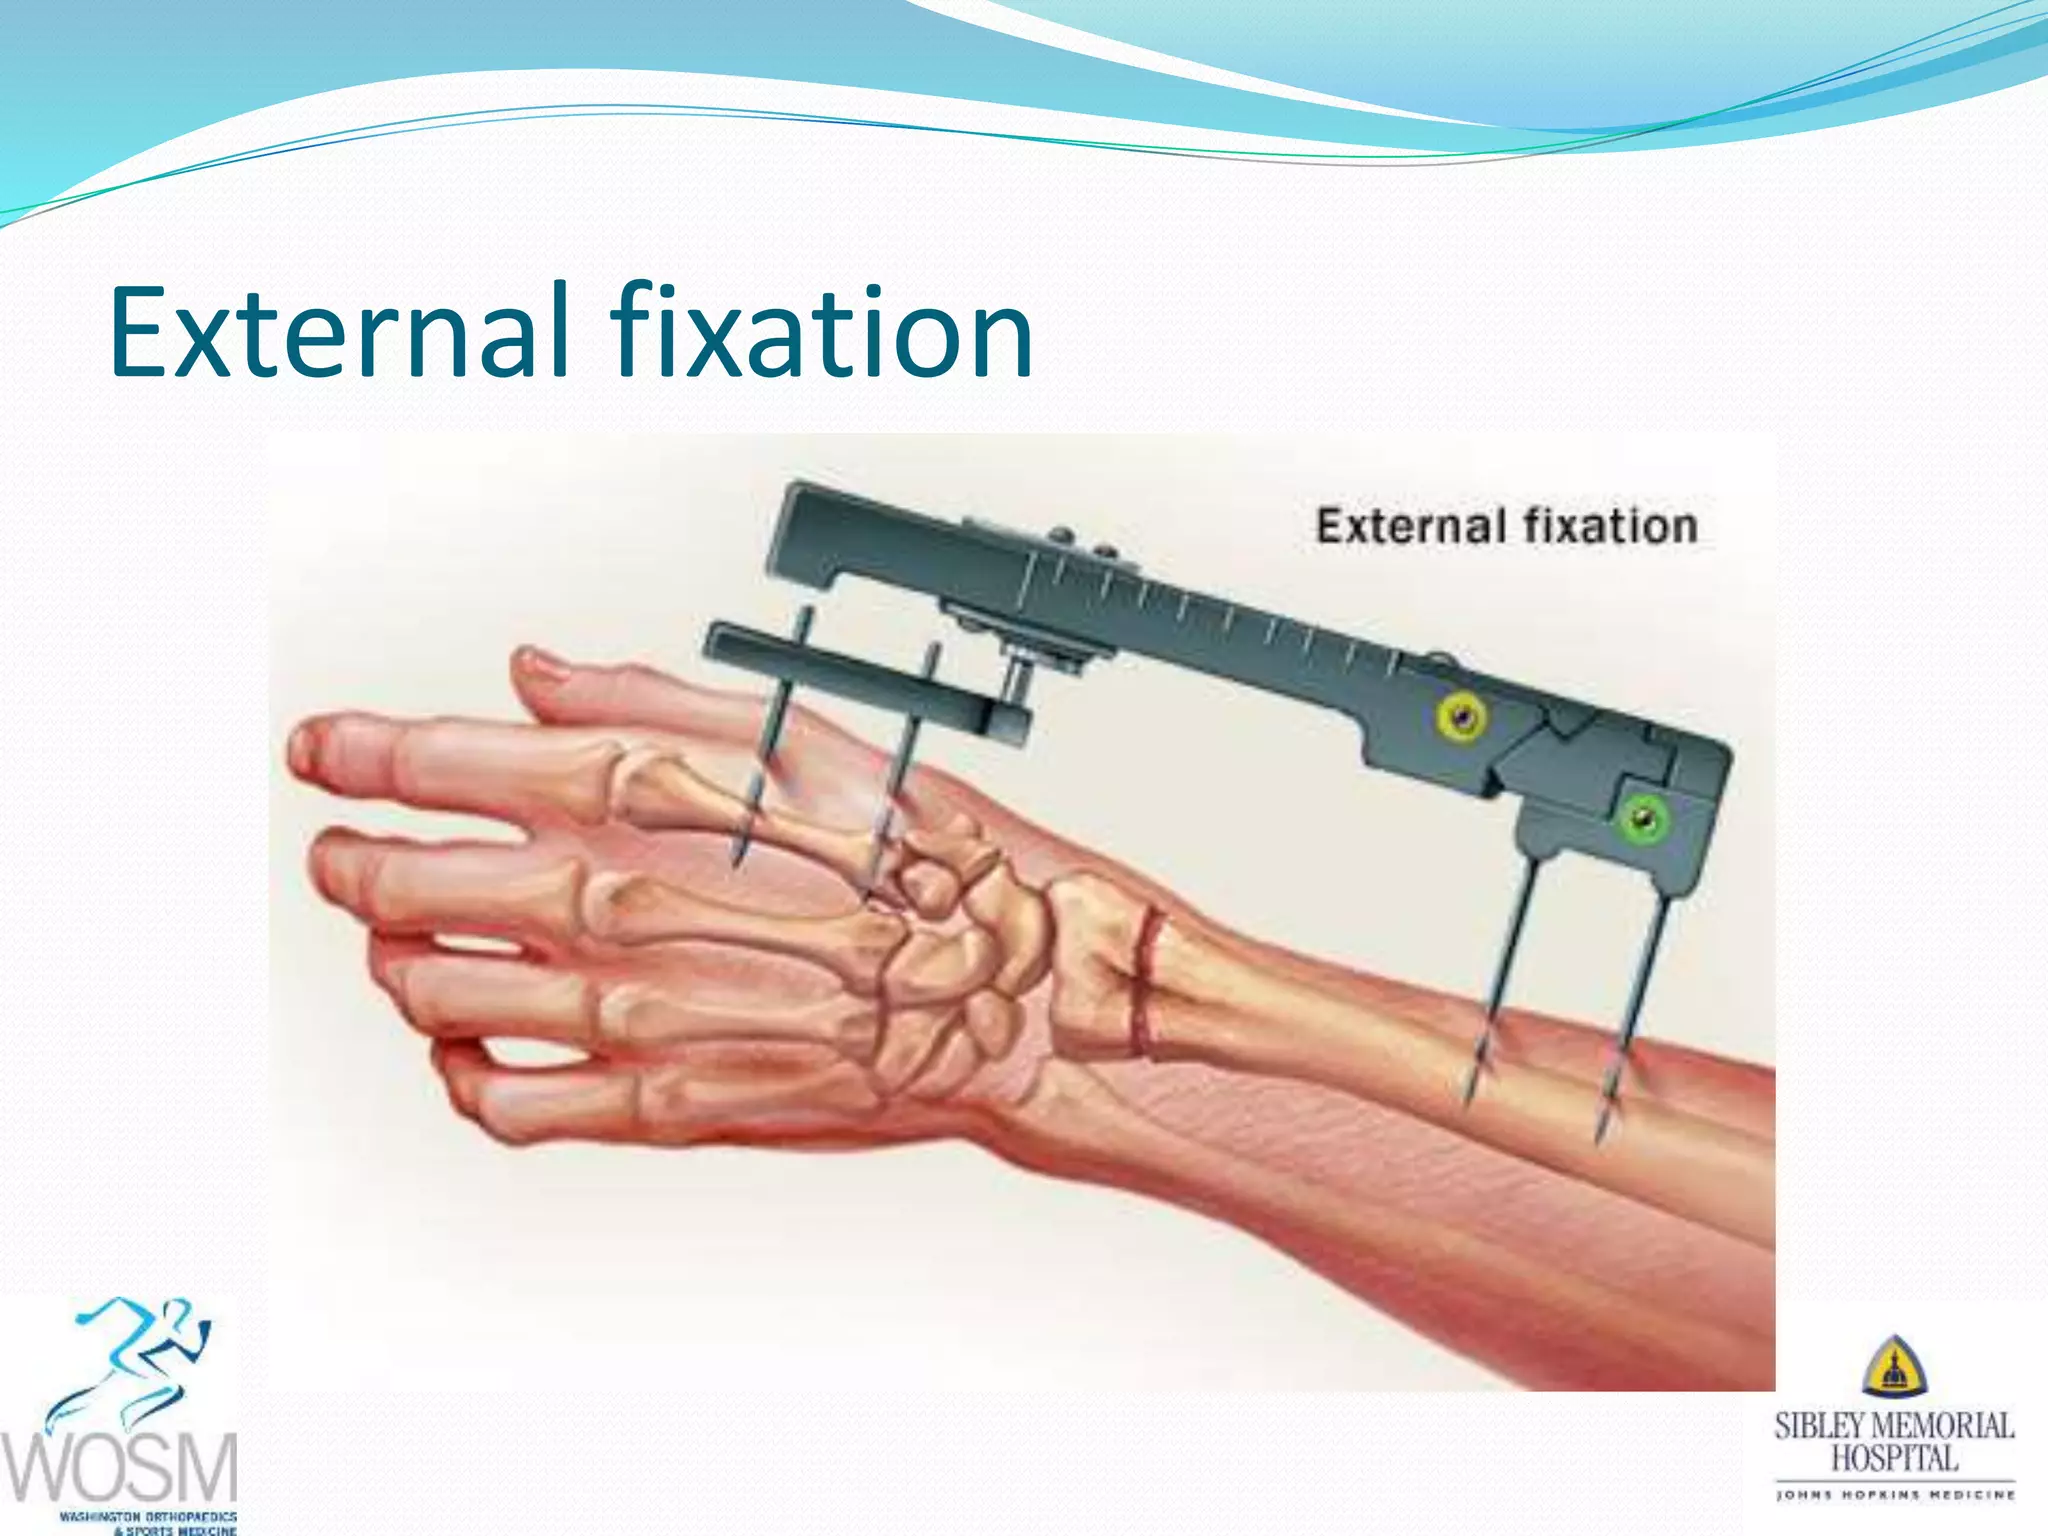

This document discusses wrist fractures, including who is most at risk, common causes, signs and symptoms, treatment options, and prevention. The elderly and those with osteoporosis are most prone to wrist fractures due to falls. Treatment may involve splinting, casting, closed reduction, or surgery depending on the fracture. Maintaining bone health through medication, vitamins, exercise, and diet can help prevent wrist fractures.